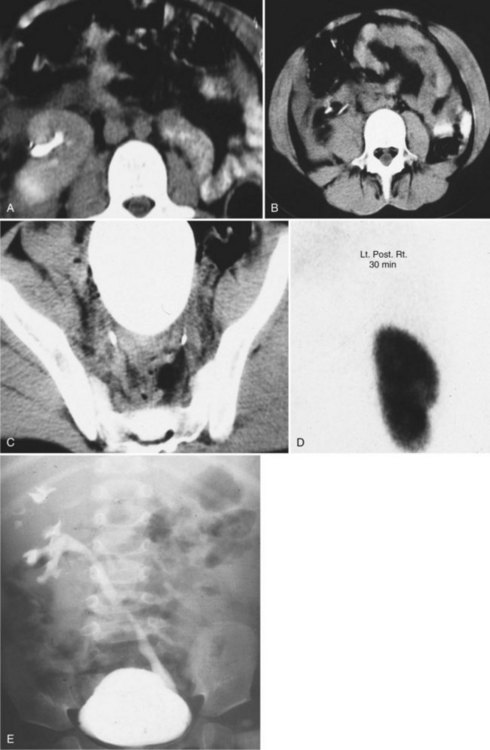

The left side is favored slightly over the right. Pelvic ectopia has been estimated to occur in 1 of 2100 to 3000 autopsies (Stevens, 1937). A solitary ectopic kidney occurs in 1 of 22,000 autopsies (Stevens, 1937; Hawes, 1950; Delson, 1975). By 1973, only 165 cases of a solitary pelvic kidney had been recorded (Downs et al, 1973). Bilateral ectopic kidneys are even more rarely observed and account for only 10% of all patients with renal ectopia (Malek et al, 1971) (Fig. 117–10).

Figure 117–10 One-day-old boy with a right retrovesical pelvic kidney demonstrated on (A) transverse ultrasonogram of right pelvis. B, Sagittal MRI. Vertebral abnormalities and a portion of a lipomyelomeningocele are also observed. C, Longitudinal ultrasonogram of left multicystic dysplastic pelvic kidney. D, Voiding cystourethrogram shows reflux into dilated, tortuous right megaureter. E, Flow study of dimercaptosuccinic acid shows early activity only in the region of the right pelvic kidney and no uptake on the left. F, Postmortem specimen from a different case showing bilateral pelvic ectopia, anterior orientation of renal pelves, and anomalous blood supply from the aortic bifurcation.

(C, Courtesy of Dr. Sara Milla; F, from Weiss MA, Mills SE. Atlas of genitourinary tract disorders. Philadelphia: JB Lippincott; 1988.)

The classification of ectopia is based on the position of the kidney within the retroperitoneum: The pelvic kidney opposite the sacrum and kidneys below the aortic bifurcation are the most common sites of ectopia; the lumbar kidney resides near the sacral promontory in the iliac fossa and anterior to the iliac vessels; and the abdominal kidney is above the iliac crest and adjacent to the second lumbar vertebra (see Fig. 117–10).

Although the contralateral kidney is usually normal, it is associated with a number of congenital defects. Malek and colleagues (1971) and Thompson and Pace (1937) reported the incidence of contralateral agenesis to be rather high (Chow et al, 2005). Bilateral ectopia occurs infrequently (10%) (see Fig. 117–10). Hydronephrosis secondary to obstruction or reflux may be seen in as many as 25% of nonectopic contralateral kidneys (Gleason et al, 1994).

With the increasing use of various imaging modalities, the incidence of an asymptomatic ectopic kidney is increasing. Most ectopic kidneys are asymptomatic. Vague abdominal complaints or ureteral colic secondary to an obstructing stone are the most frequent symptoms leading to the diagnosis of an ectopic kidney. The abnormal position of the kidney results in a pattern of direct and referred pain that is atypical for colic and may be misdiagnosed as acute appendicitis or as pelvic inflammatory disease in female patients. Symptoms rarely occur due to adjacent organs to the ectopic kidney. Renal ectopia may also present with a UTI or a palpable abdominal mass. Seven cases of concomitant renal and ureteral ectopia presenting with urinary incontinence have been reported (Borer et al, 1993, 1998). The difficulty in diagnosing this condition is related to the poor function of these ectopic kidneys. The kidneys may be very small and/or dysplastic with essentially no function leading to the misdiagnosis of URA. DMSA scanning or MR urography may both be necessary to diagnose these unusual cases (Borer et al, 1998; Leitha, 1998; Pattaras et al, 1999) (see Fig. 117–10).